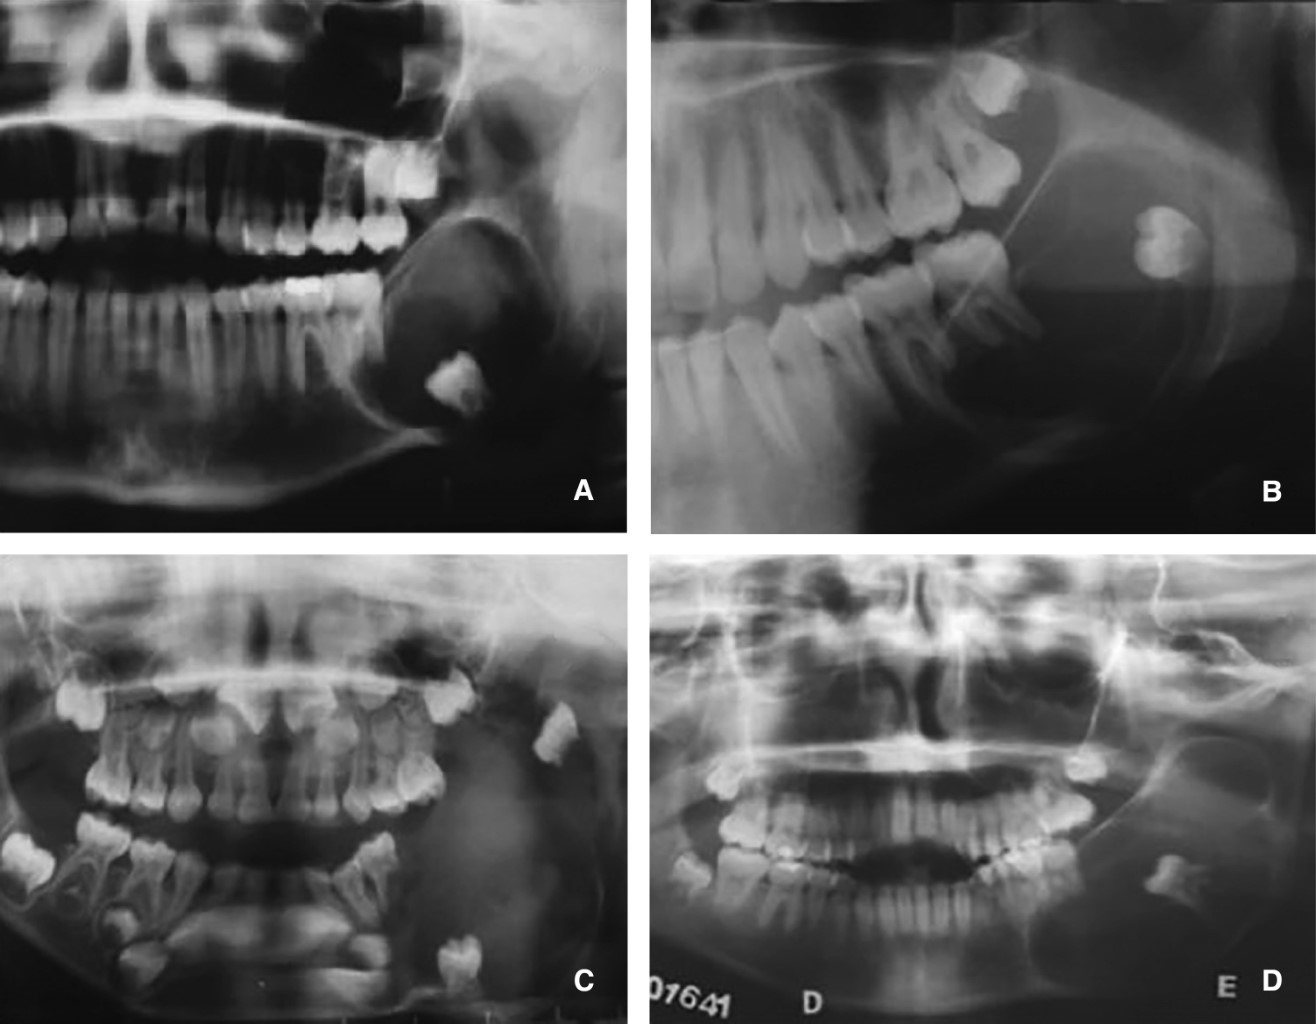

Introduction: the primordial odontogenic tumor (POT) is a rare odontogenic tumor. The World Health Organization (WHO) in 2017 and 2022 classified it as a benign, mixed neoplasm. To date, only 23 cases have been documented in the world. Objectives: to analyze clinical and radiographic histopathological characteristics and treatment reported to date. Material and methods: an exhaustive electronic search was carried out in august and September of the year 2022, with date restrictions from 2014 where the TOP was reported for the first time. PubMed and ScienceDirect databases were accessed. Results: a total of 16 publications were included, representing 23 reported cases of TOP. Conclusions: TOP is a benign mixed odontogenic neoplasm, with prevalence in the first two decades of life, it presents clinically as an increase in volume, mainly mandibular and asymptomatic. Radiographically, a unilocular or multilocular lesion associated with an unerupted tooth is observed. Due to its low prevalence, it is essential to carry out a complete clinical, radiographic and histopathological study for the definitive diagnosis of this pathology. The treatment of choice is enucleation and extraction of the affected tooth. Larger studies with long-term follow-up are needed to create a strict treatment protocol, since few cases have been reported to date.

Figure 1